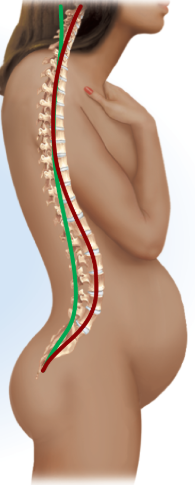

Cervical curvature

Lordosis, convex anteriorly, curves forward

Thoracic curvature

Kyphosis, concave anteriorly, curves outward

Lumbar curvature

Lordosis, convex anteriorly, curves forward

Pelvic curvature

Kyphosis, concave anteriorly, curves outward

Scoliosis

Lateral (S shape, side-to-side), thoracic region

Kyphosis

Exaggeration of thoracic curvature, overly rounded (shrimp posture)

Lordosis

Exaggeration of lumbar curvature, too far forward